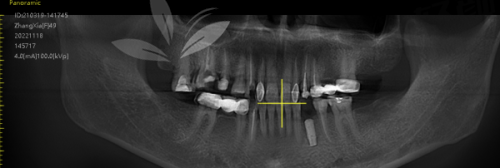

二、泰康拜博口腔医院种植牙价格明细:从三四千到一万多都有,看你选啥!

种植牙的价格一听就头大?我们来拆解一下这波“看似复杂其实花样多”的项目!简直比彩妆套装还细分!

种植体品牌价格(元/颗)

韩国登腾种植体3980元~6980元

法国安卓健种植牙6800元~8800元

美国皓圣全套(含牙冠)6800元~9000元

德国camlog种植体9500元~13000元

瑞士ITI进口种植体12000元~15800元

瑞典Nobel种植体13800元~18000元

以色列MIS/Alpha Bio种植体10500元~13800元

All-On-4/半口种植3.5万元起

全口种植牙(12-14颗)8万~16万起

笑出声:种植价就像酒店价格,从快捷店到总统套房,应有尽有。关键看你选的“床位”——有的经济实惠(登腾),有的全套贵族体验(Nobel牙冠+进口基台)